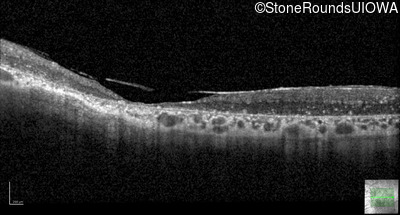

Optical Coherence Tomography - Left - Light Perception

Exemplar / OCT Stack

Optical Coherence Tomography - Left - 20/600 sc